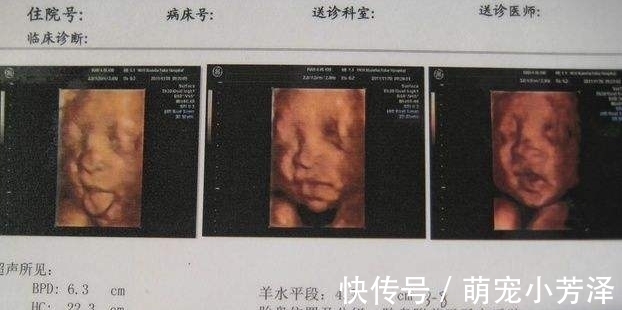

4.四维直接看到胎宝

四维彩超和b超一样,是用超声波通过腹部把宝宝的图像投射到电脑上。这种成像技术是为了检查婴儿的器官是否变形,而不是为了让婴儿看起来更好。所以不好看很正常。四维彩超并没有自带美颜,宝宝不好看也是合理的。